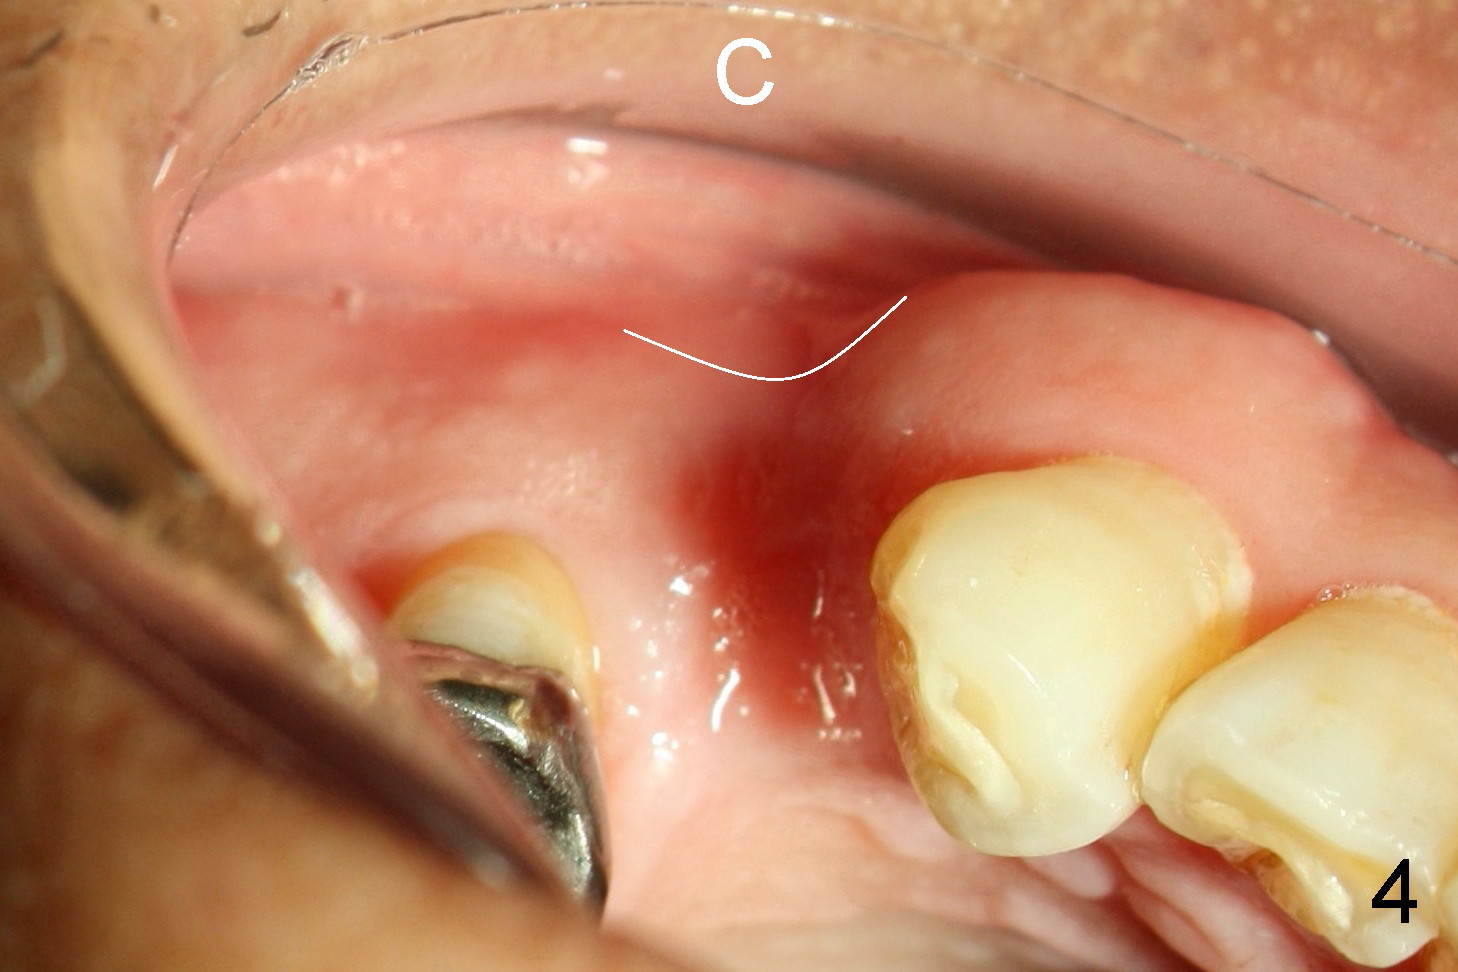

A 68-year-old man has pain and swelling associated with the tooth #5 (Fig.1). The fistula (*) is connected to the periapical radiolucency using a gutta percha (Fig.2 <). There are deep pockets distobuccal and lingual. The lingual root is found to have oblique fracture upon extraction. The distobuccal plate perforates (Fig.3). Collagen plug is placed. The buccal plate is concave (Fig.4) and socket density is low 2.5 months post extraction. Three months post extraction a 4.5x8 mm Bicon implant is placed after reamer and osteotome osteotomy (Fig.6). Bone density around the implant appears to increase 5 months post placement (Fig.7). Porcelain-fused-to-metal crown is cemented 2 weeks later. Bucco-occlusal porcelain chips 2 months post cementation. The patient decides to redo the crown. PA is taken before crown removal (Fig.8: 3 year 10 months post cementation). When a straight abutment is removed (Fig.9 A), a 15° angled abutment has to be used (Fig.10 red) for restoration.